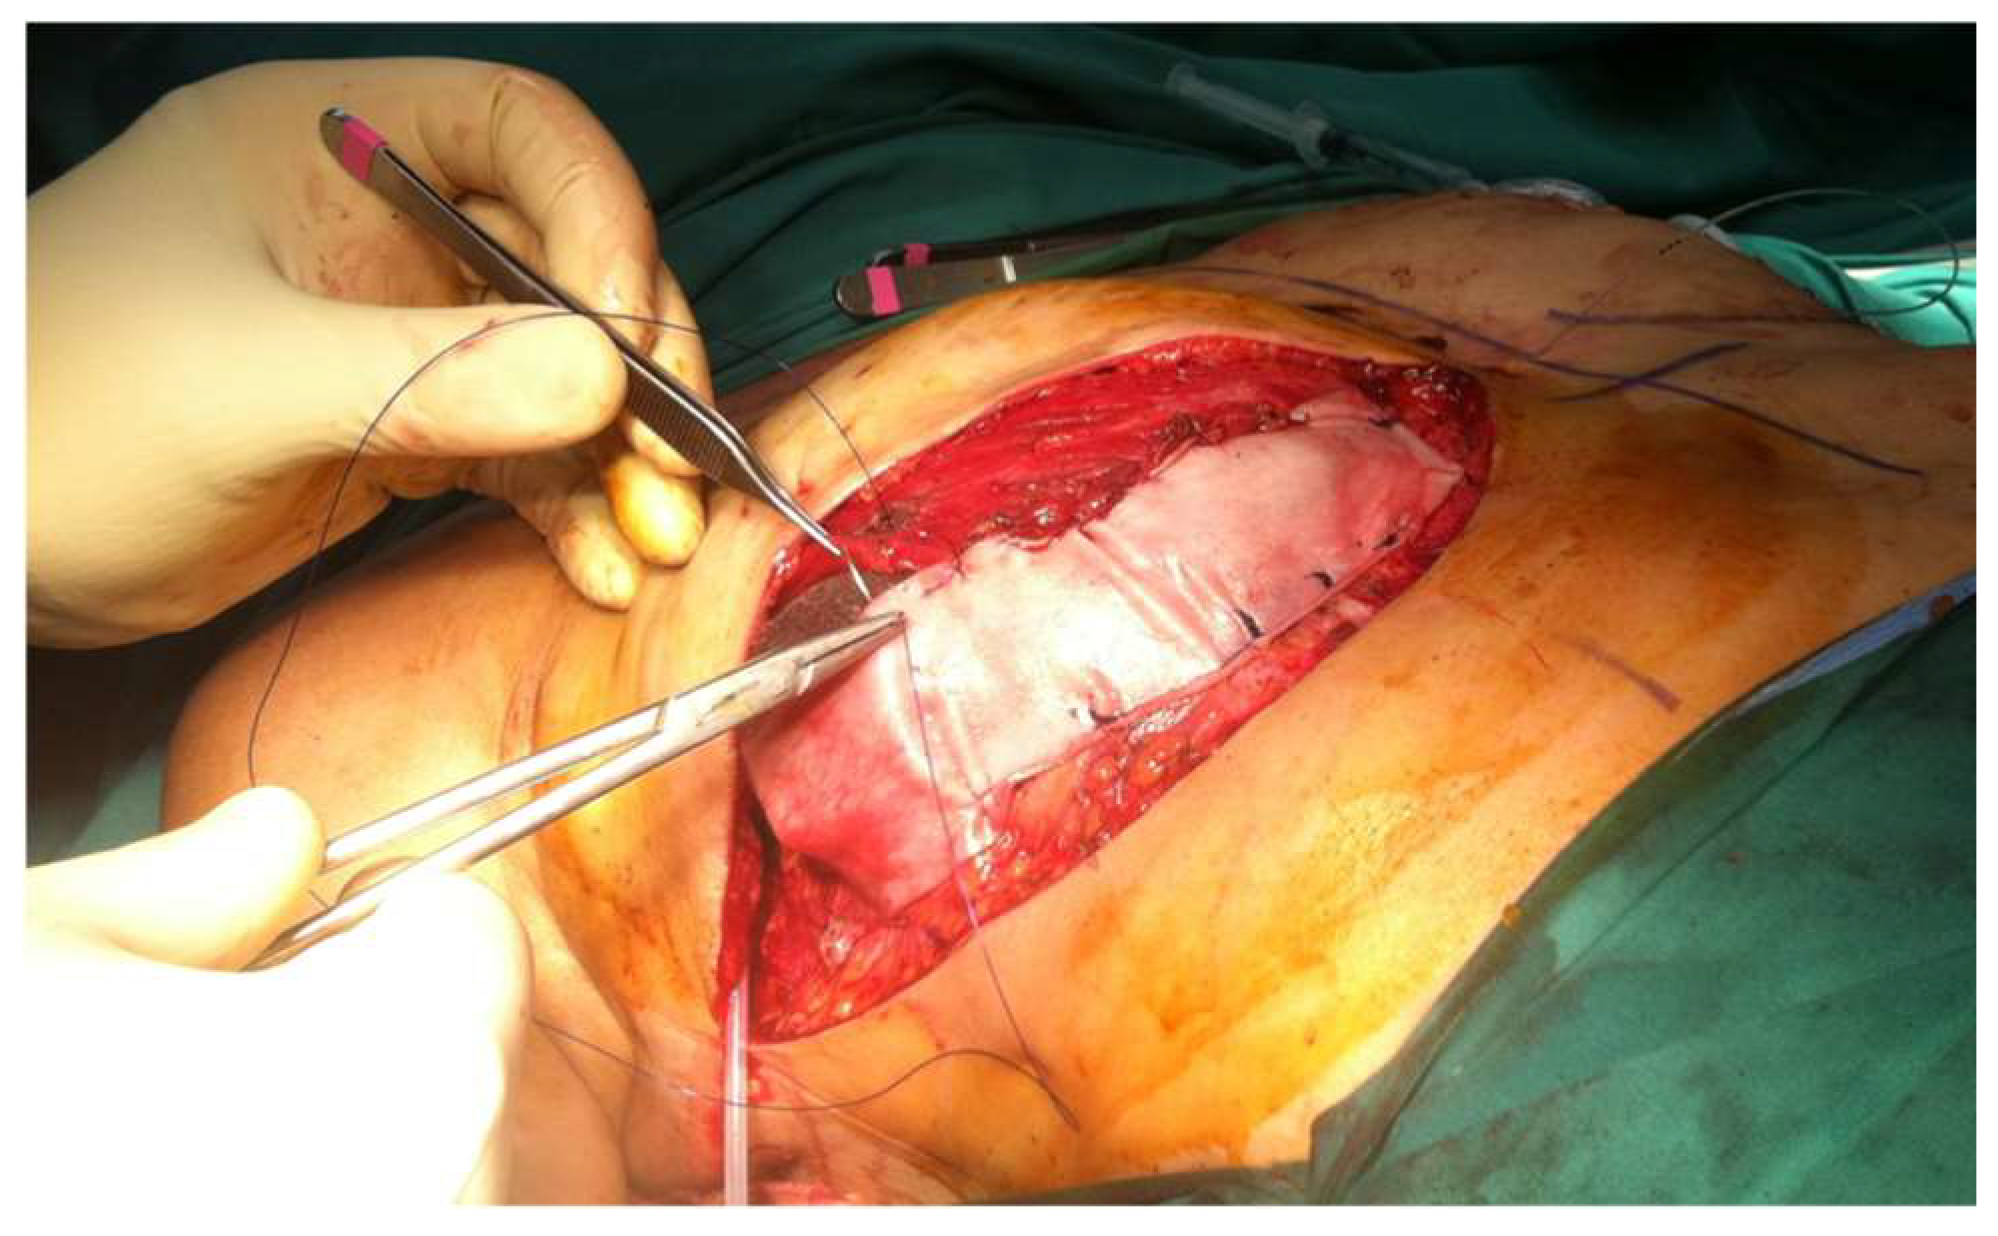

2.1.3. Muscle Sparing Free Flaps

2.2.2. Acellular Dermal Matrices (ADMs)